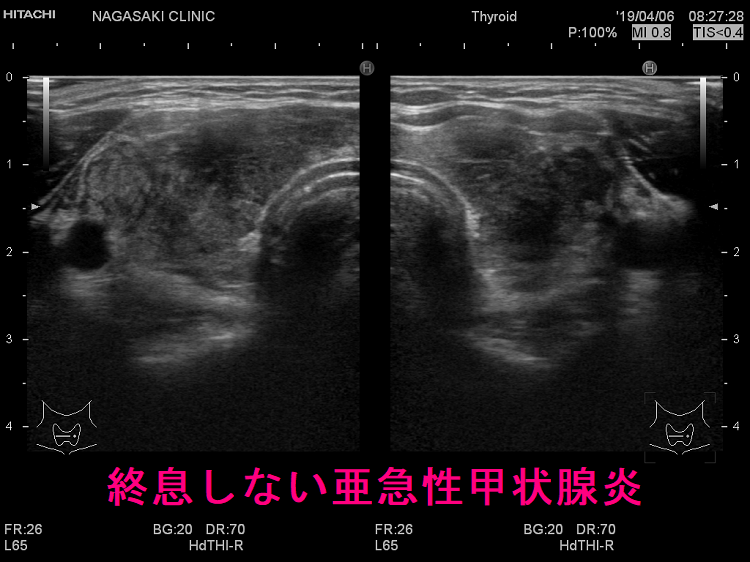

「数年かかっても完全治癒しない亜急性甲状腺炎が存在する」と言われれば、「別の病気を亜急性甲状腺炎と間違えてるんちゃうん?例えば、甲状腺悪性リンパ腫など。」と誰しもが思います。筆者も、そう考えていました。しかし、現実にそのような症例は存在するのです。

亜急性甲状腺炎は通常、数ヶ月の経過で治癒します。しかし稀に、一度寛解しても数か月経つと別の場所に病変が現れ、再度ステロイド投与で治癒しては、数か月後に再燃を繰り返す悪夢のような亜急性甲状腺炎が存在します。

筆者も自分自身で、そのような症例に遭遇するまで信じられませんでした。筆者自身が経験した症例は、ステロイド剤が著効し、数カ月でエコー上、亜急性甲状腺炎の炎症部(低エコー領域)が完全に消失し治癒するが、1-2カ月で違う場所に痛みを伴う低エコー領域が出現し、何度もステロイド剤投与を繰り返すものでした。

他の甲状腺クリニックも、途中で数回再発を繰り返し、2年かけて沈静化した亜急性甲状腺炎の症例を報告していました(第57回 日本甲状腺学会P2-059 治癒までに2 年かかった亜急性甲状腺炎の一例)。筆者の経験と同じく、次々と甲状腺内の違う場所に病変が時間差を置いて出現し、「甲状腺全体に炎症が広がるまで終息しない亜急性甲状腺炎なのか?」と考えざる得ません。

元々、亜急性甲状腺炎は、甲状腺すべてに炎症が波及しないと終わらないのか?

「亜急性甲状腺炎は、甲状腺すべてに炎症が波及しないと終わらない」との説があります。前項の 本当に存在する数年かかっても完全治癒しない亜急性甲状腺炎 はその典型例と言えます。